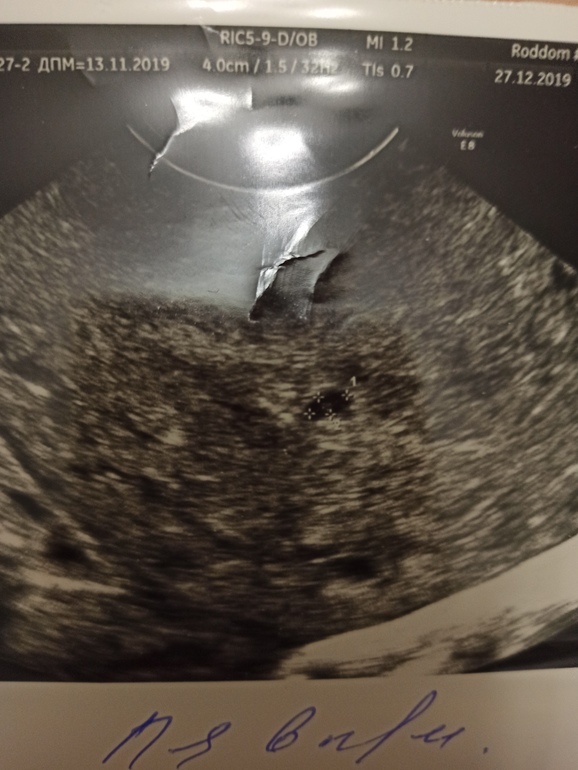

Вот УЗИ от 27 декабря

, где яйцо деформировано, с отслойками и сгустками, в заключении написано вот:

31 декабря вышли куча сгустков и море крови и после ничего, ни мазни, вообще ничего, чистые выделения.

И вот сегодня пошла снова на УЗИ, чтобы убедиться в том, что всё вышло. Но на УЗИ нет ни сгустков, ни отслоек, внутри обычная беременность малого срока, обычный эндометрий, яйцо не деформировано, что прикреплено хорошо. И сказала узист, что если бы я не показала предыдущее УЗИ и не рассказала про выделения, то она бы была уверена, что эта беременность нормальная.

И узист и врач склоняются к мнению, что это другое ПЯ, что было два зачатия(второе позже) и первое ПЯ вышло.

Но вроде расположение ПЯ на первом на втором снимках разное. Похоже, что это действительно два разных.

Тем более это ПЯ хорошее, ровненькое, видно, что там либо зачаток эмбриона, либо желточный мешочек. Матка в адеквате, без сугустов и прочего лишнего, в отличие от прового узи, там прям видно, что она вся в сгустках.